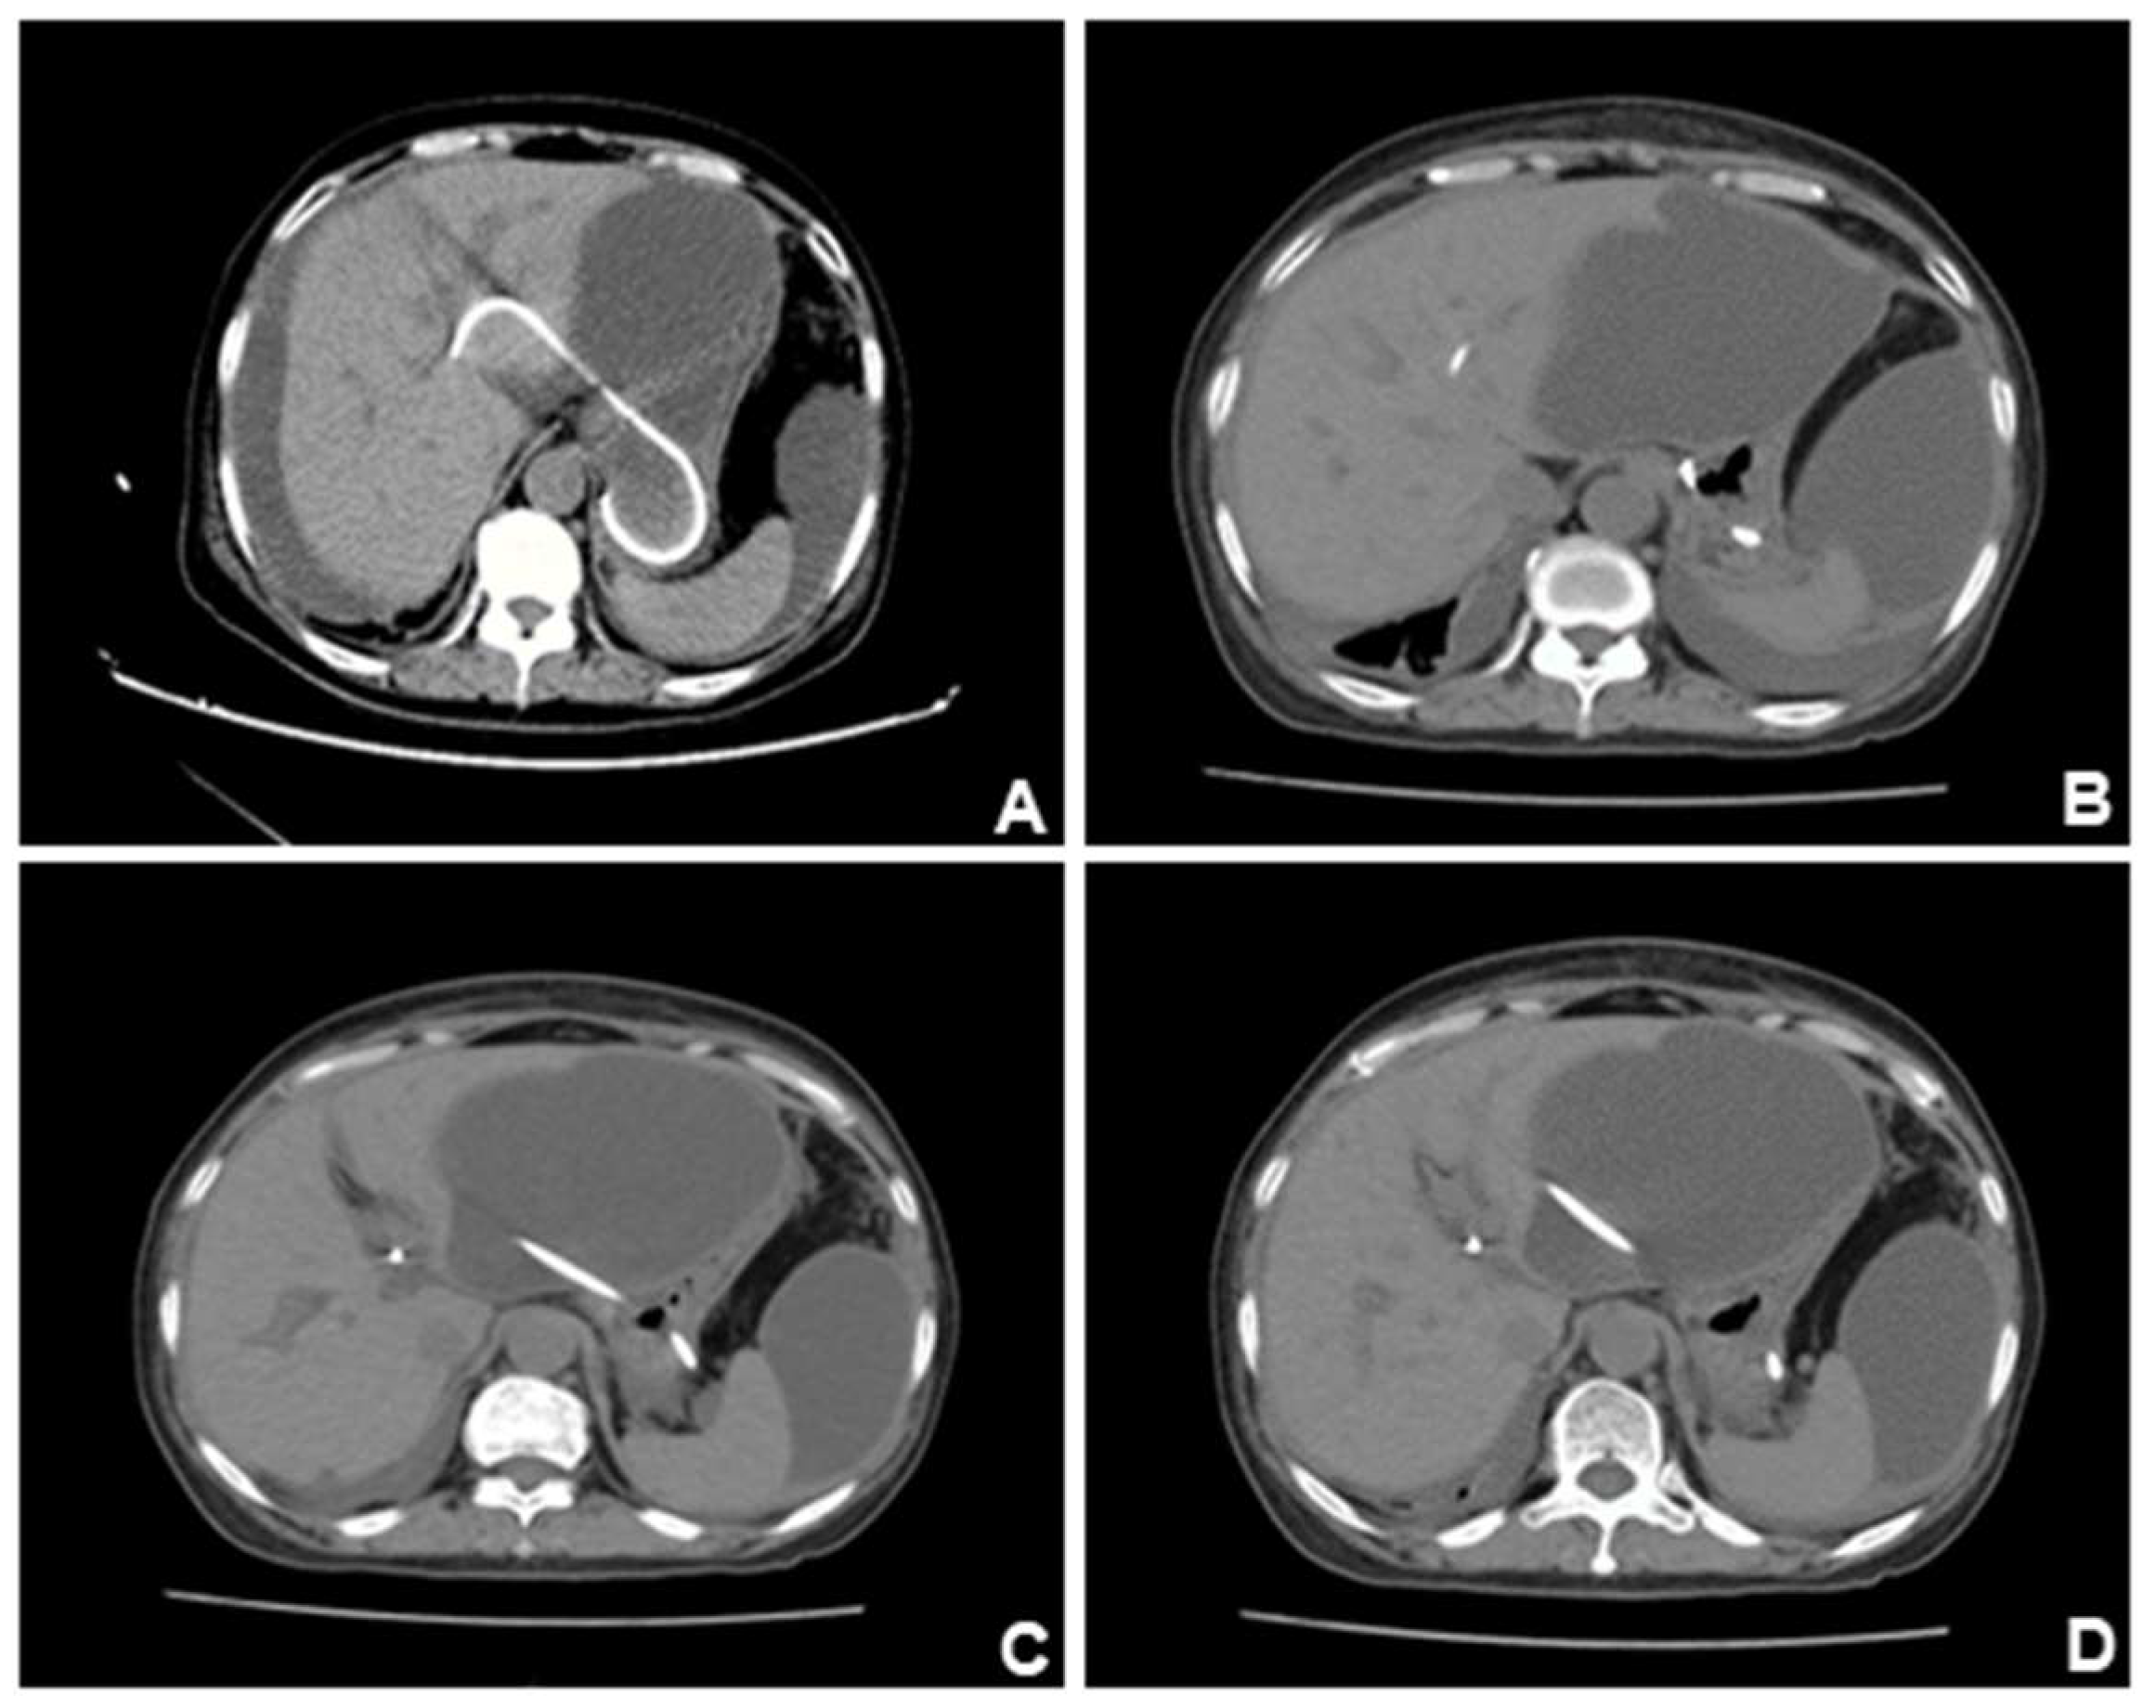

The patient reported abdominal pain and chest tightness in the next afternoon with difficulty in urinating and emergency CT of the chest was performed(A-B). CT results suggestive of right pleural effusion and right lower lobe lung atelectasis. (C-D). The stent was shown to be well-positioned under CT. We suspected that the patient's pleural effusion may have been caused by accidental injury to the diaphragm during the puncture procedure. After chest drainage was performed, the bilateral lung fields returned clear and showed no substantial lesions.